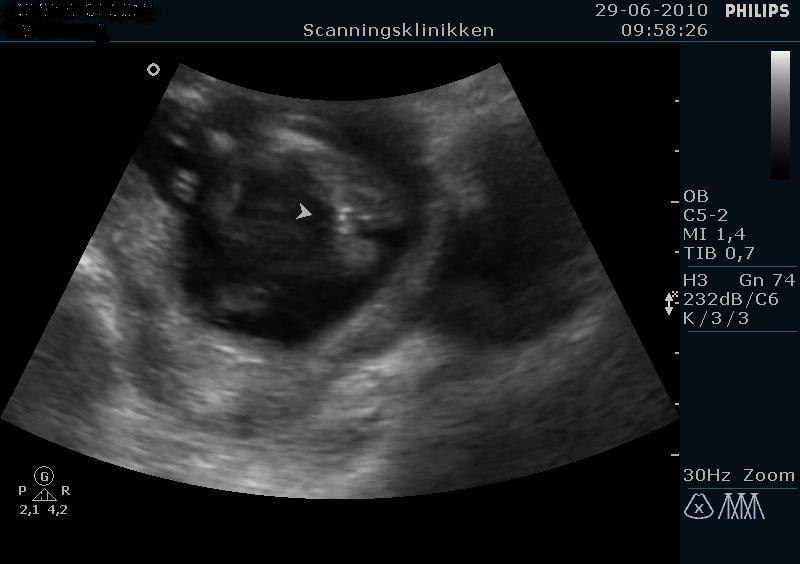

Vi fik lavet kønsscanning da jeg var 17+0 og hun kiggede længe fordi den lille drillede, til sidst sagde hun bare at nu var hun helt sikker, og det var en pige. Hvis du kan se på dine billeder, så skulle det vidst være meget nemt og se om der er tap eller ej. Her havde vi 2 tydelige streger, og en lille tynd streg i midten. De 2 tydlige viser de ydre skamlæber, og den lille tynde streg er de indre skamlæber.